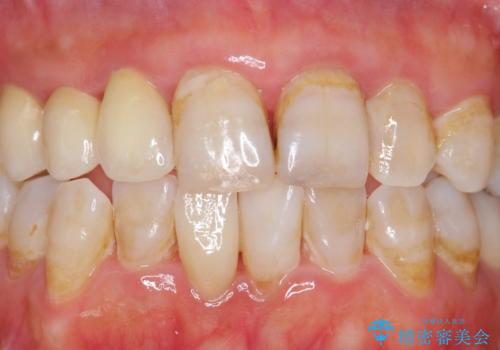

- 被せ物がかけてしまったことを主訴に来院された患者様です。

口腔内を精査したところ、右上のブリッジの内側(口蓋側)がかけており、下の前歯(右下1)には唇舌側に瘻孔を伴う大きな根尖病変ができていました。

右上のブリッジ(右上④3②)のやりかえと、下の前歯(右下1)の根管治療を行った後セラミッククラウンによる補綴治療を行いました。